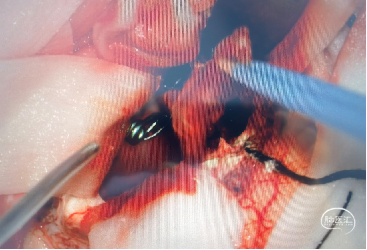

2022-10-28 神经外科 急诊显微手术

阻断主供血动脉:左侧大脑后动脉分支

清除血肿,阻断大脑中动脉分支、脑膜支后,尝试阻断引流静脉,畸形团立即出血

探查静脉瘤、静脉湖底面折返的供血动脉

最后阻断引流静脉,畸形团干瘪

2022-10-28 动静脉畸形切除标本